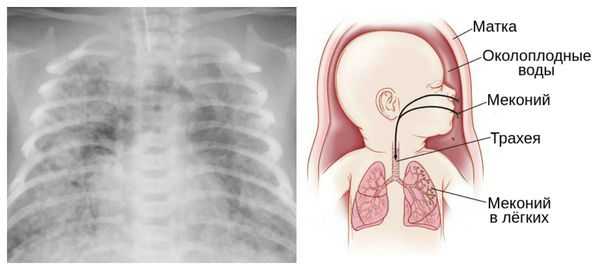

зеленый цвет околоплодных вод в более поздние сроки - за счет окрашивания меконием;

Из-за снижения кровотока в почках плода выделение мочи значительно уменьшается, развивается маловодие. Также изменяется характер околоплодных вод: они теряют прозрачность, становятся мутными, приобретают желтоватый или зеленоватый оттенок из-за примеси мекония — первых фекалий ребёнка.

Осложнения перенашивания беременности

Для плода большую опасность представляет асфиксия (острая гипоксия) и отслойка плаценты. Нехватка кислорода внутри утробы стимулирует плод выполнить несвоевременные дыхательных движения. Они приводят к заглатыванию вод и возможному воспалению лёгочной ткани — пневмониту. Если в водах есть примесь мекония (первородного кала), то велика вероятность мекониальной аспирации — проникновения содержимого кишечника новорождённого в его лёгкие.